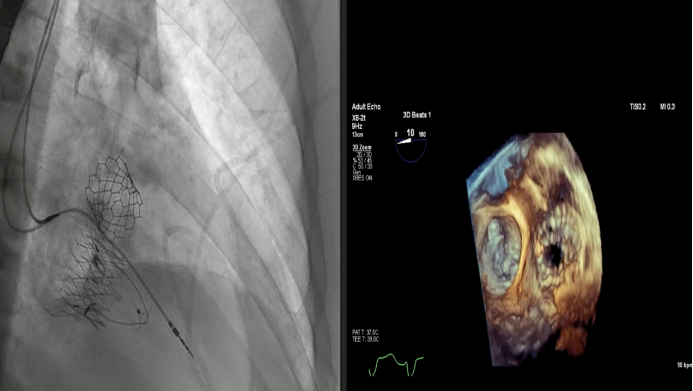

Dee Dee Wang教授分享了Henry Ford Hospital前4例Lux-Valve Plus的植入經驗,并提示術中確定瓣葉夾持鍵的位置處于三尖瓣瓣環(huán)下方(右心室側),以及室間隔固定片與室間隔的相對位置關系是最關鍵的兩個步驟。使用經胃底短軸切面,有時配合右室流入/流出道切面的X-plane就能較容易地獲取相關影像。由于Lux-Valve Plus對超聲影像的要求較低,手術過程會相對比較流暢。

術后結果